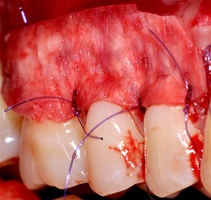

1. Генерализованные рецессии в области нижней челюсти оперировались в один этап все 12 зубов, фронтальный участок с аутотрансплантатом от 3.2 до 4.2 зубов. А дистальные участки от 3.6 до 3.3 и от 4.6 до 4.3 зубов с использованием пластического материала ТМО (dura mater) (рис. 4а-з).

3.2-4.2 зубы были прооперированы методом, сочетающим вестибулопластику с одновременным увеличением ширины и толщины прикрепленной десны при помощи свободного десневого аутотрансплантата (операция Bjorn, 1963 г.).

1. Подготовка принимающего ложа. Включает в себя формирование полнослойно-расщепленного слизисто-надкостничного лоскута (полнослойного в области зенитов рецессий, расщепленного билатерально области рецессии десны), рассечение и отслаивание слизисто-мышечных волокон вестибулярно ниже мукогингивальной границы, деэпителизация межзубных сосочков.

2. Обработка поверхностей корней зубов. Включает ультразвуковую обработку скейлером для очищения от минерализованных зубных отложений и мягкого зубного налета, экспозицию геля ЭДТА 17% в течение двух минут, механическое удаление слоя бесклеточного цемента импрегнированного микроорганизмами зоноспецифическими кюретами, полировку пародонтологическими борами («фасолька» и «обратный треугольник»).

3. Получение аутотрансплантата: начинается с определения толщины донорской зоны и замеров размера будущего трансплантата. Зона забора от второго премоляра до третьего моляра верхней челюсти. Глубина погружения брюшка скальпеля 2 мм, далее трансплантат оптимизируют — деэпителизируют по периметру.

4. Затем проводиться позиционирование аутотрансплантата в области рецессий и принимающего ложа двумя-тремя узловыми швами; после аутотрансплантат стабилизируют прижимающими двумя-четырьмя матрасными крестообразными швами, что позволит плотно прижать аутотрансплантат и избежать образования «мертвых» зон для питания аутотрансплантата.